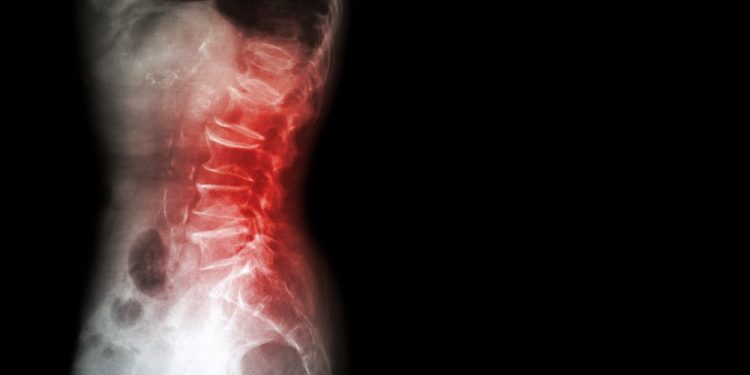

The standard test used to measure bone density is the dual energy x-ray absorptiometry (DEXA) scan. The scan determines how well your bone mineral density matches that of an average young adult. If the scan is low, you are likely to have osteopenia. It may also indicate that you are at risk for fractures. If you are at risk for osteopenia, you will need to see a healthcare provider to monitor your bone mineral density. If your BMD is low, you may need to take medication to keep your bones healthy.

Osteopenia is usually diagnosed by a bone density test. If your BMD is below the average for your age group, you are at risk for osteoporosis. You should see your doctor at least once a year to check for osteoporosis and other conditions that may affect bone density. Your doctor may recommend medications to help build your bones back up, especially if you have a family history of osteoporosis or are at risk for fractures.